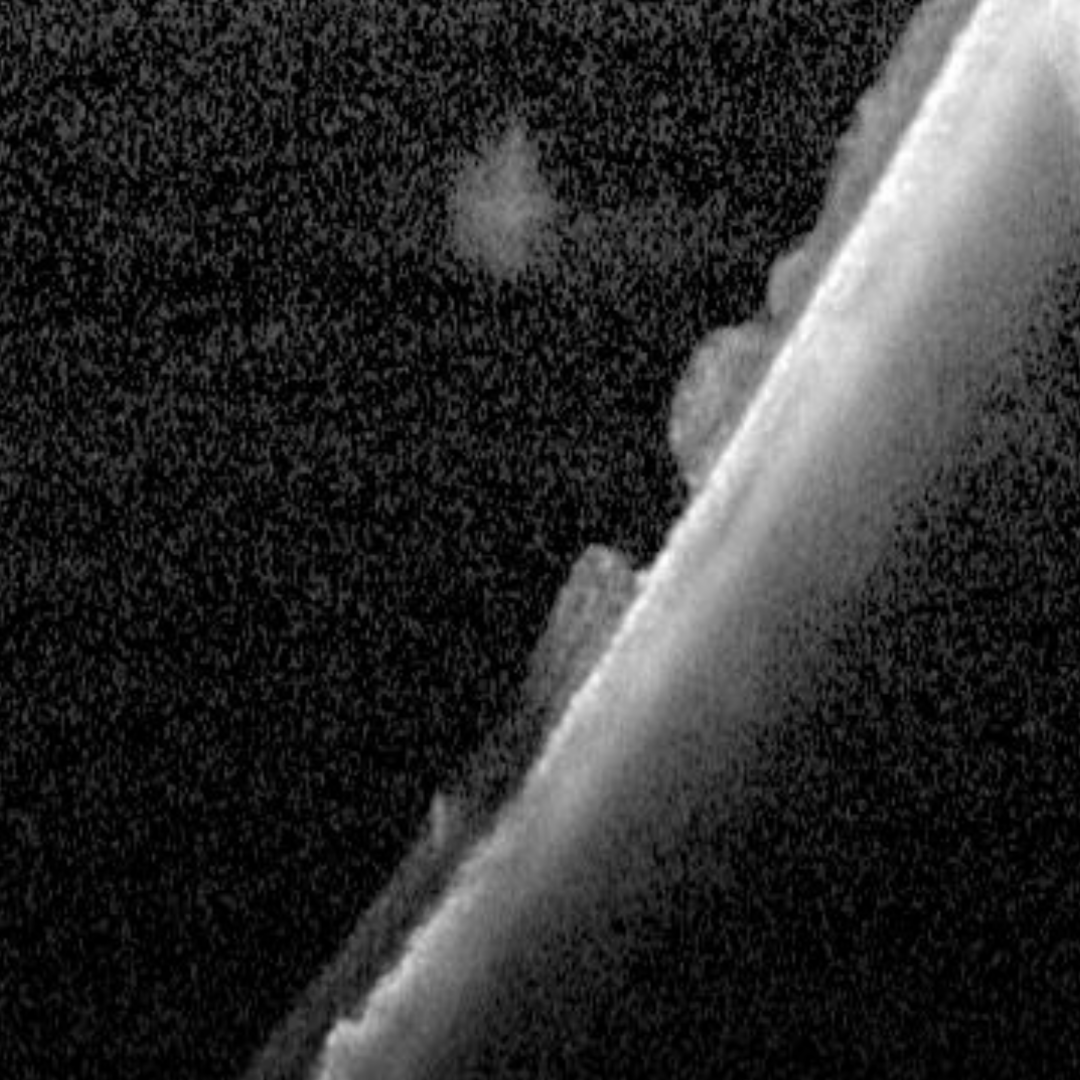

OCT shows a full thickness retinal break with the operculum often visible in the vitreous overlying the hole. The retinal hole may have subretinal fluid adjacent.